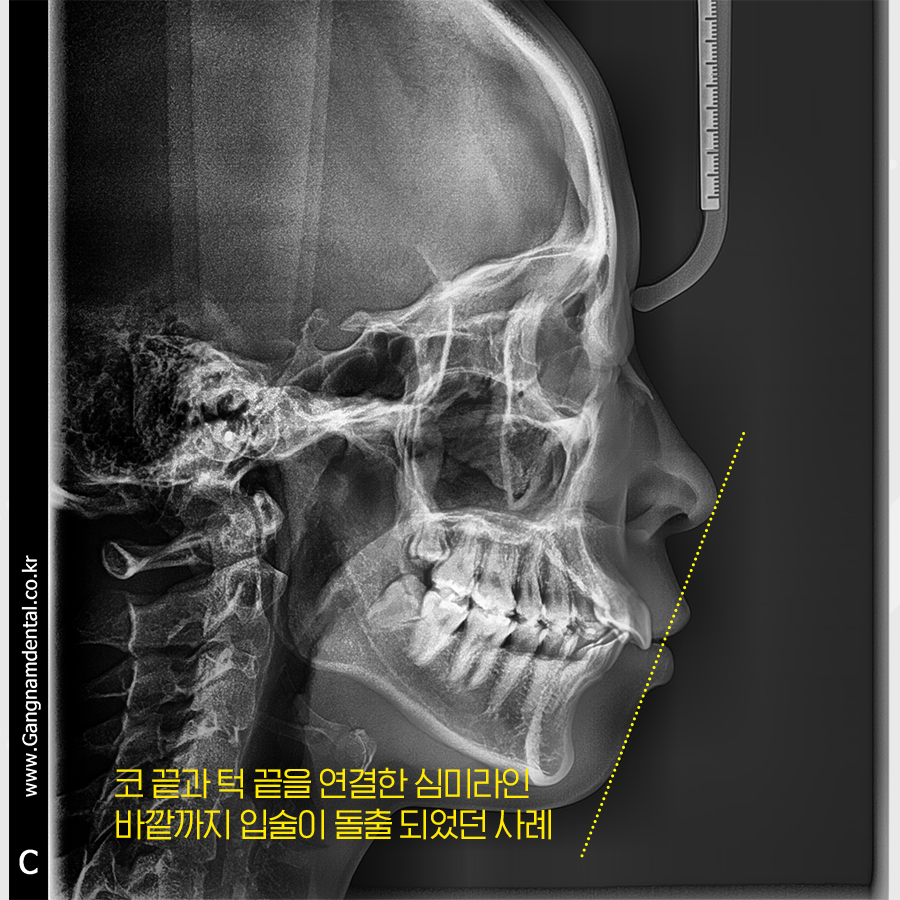

이 환자분께서는 잇몸뼈 위치나 교합 등

다른 부분엔 큰 문제가 없고

앞니 각도만 개선하면 되는 케이스여서

치아교정 만으로도 비교적 드라마틱한 결과를

받아보실 수 있을거라 진단이 되었어요.

이미 치아들이 잇몸뼈의 자리를

꽉 메우고 있는 상태에서

앞니 각도를 뒤로 기울이려니

공간이 부족한 상황!

발치 교정이 불가피했어요.

위,아래 및 좌우 작은어금니 하나씩 발치 후

공간을 만들어 냈고

전치부 치아를 전체적으로 뒤로 이동하며

중절치의 각도를 조정했습니다.

옆모습만 보더라도 돌출입이

상당히 많이 들어간 모습을 확인할 수 있죠?